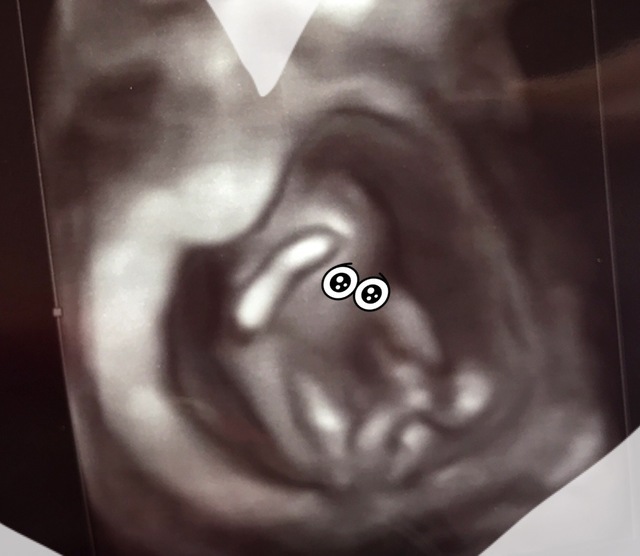

12週6日(12w6d・男の子)|chaa1015 さん(30歳)

エコー写真撮影時のエピソード:

4Dでの初めての撮影です。 普通のエコーと比べてとてもリアルで記念の1枚です!

検査中に手が動いている姿に夫と一緒に感動しました!4Dだからわかりやすいとは思いますが、どこがお顔かよくわかるように目をつけて両親などに報告しました。